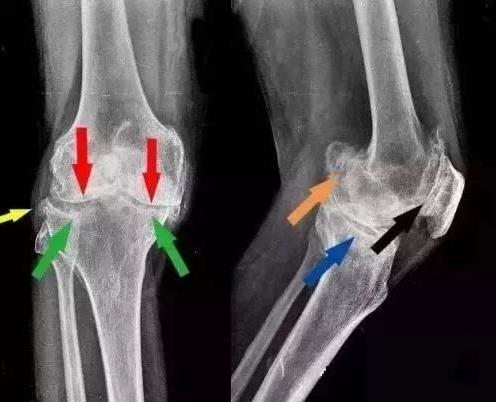

【摘要】骨质增生,又称骨刺,是困扰中老年人的一种常见的骨科疾病,严重影响人们的生活和工作,得了骨增生那怎么治疗呢?

骨质增生,又称骨刺,是困扰中老年人的一种常见的骨科疾病,严重影响人们的生活和工作,得了骨增生那怎么治疗呢?

3.及时治疗骨关节疾病

骨折和外伤也是成骨发生的重要诱因,两者都可导致创伤性关节炎,尤其是骨折复位不全,容易造成关节软骨表面不平,从而发生成骨。因此,一旦出现上述问题,就要及时就医,及时诊断和治疗创伤性关节炎,避免关节发生骨质发生。另外,对于骨质增生的患者,要及时就医,防止病情恶化。